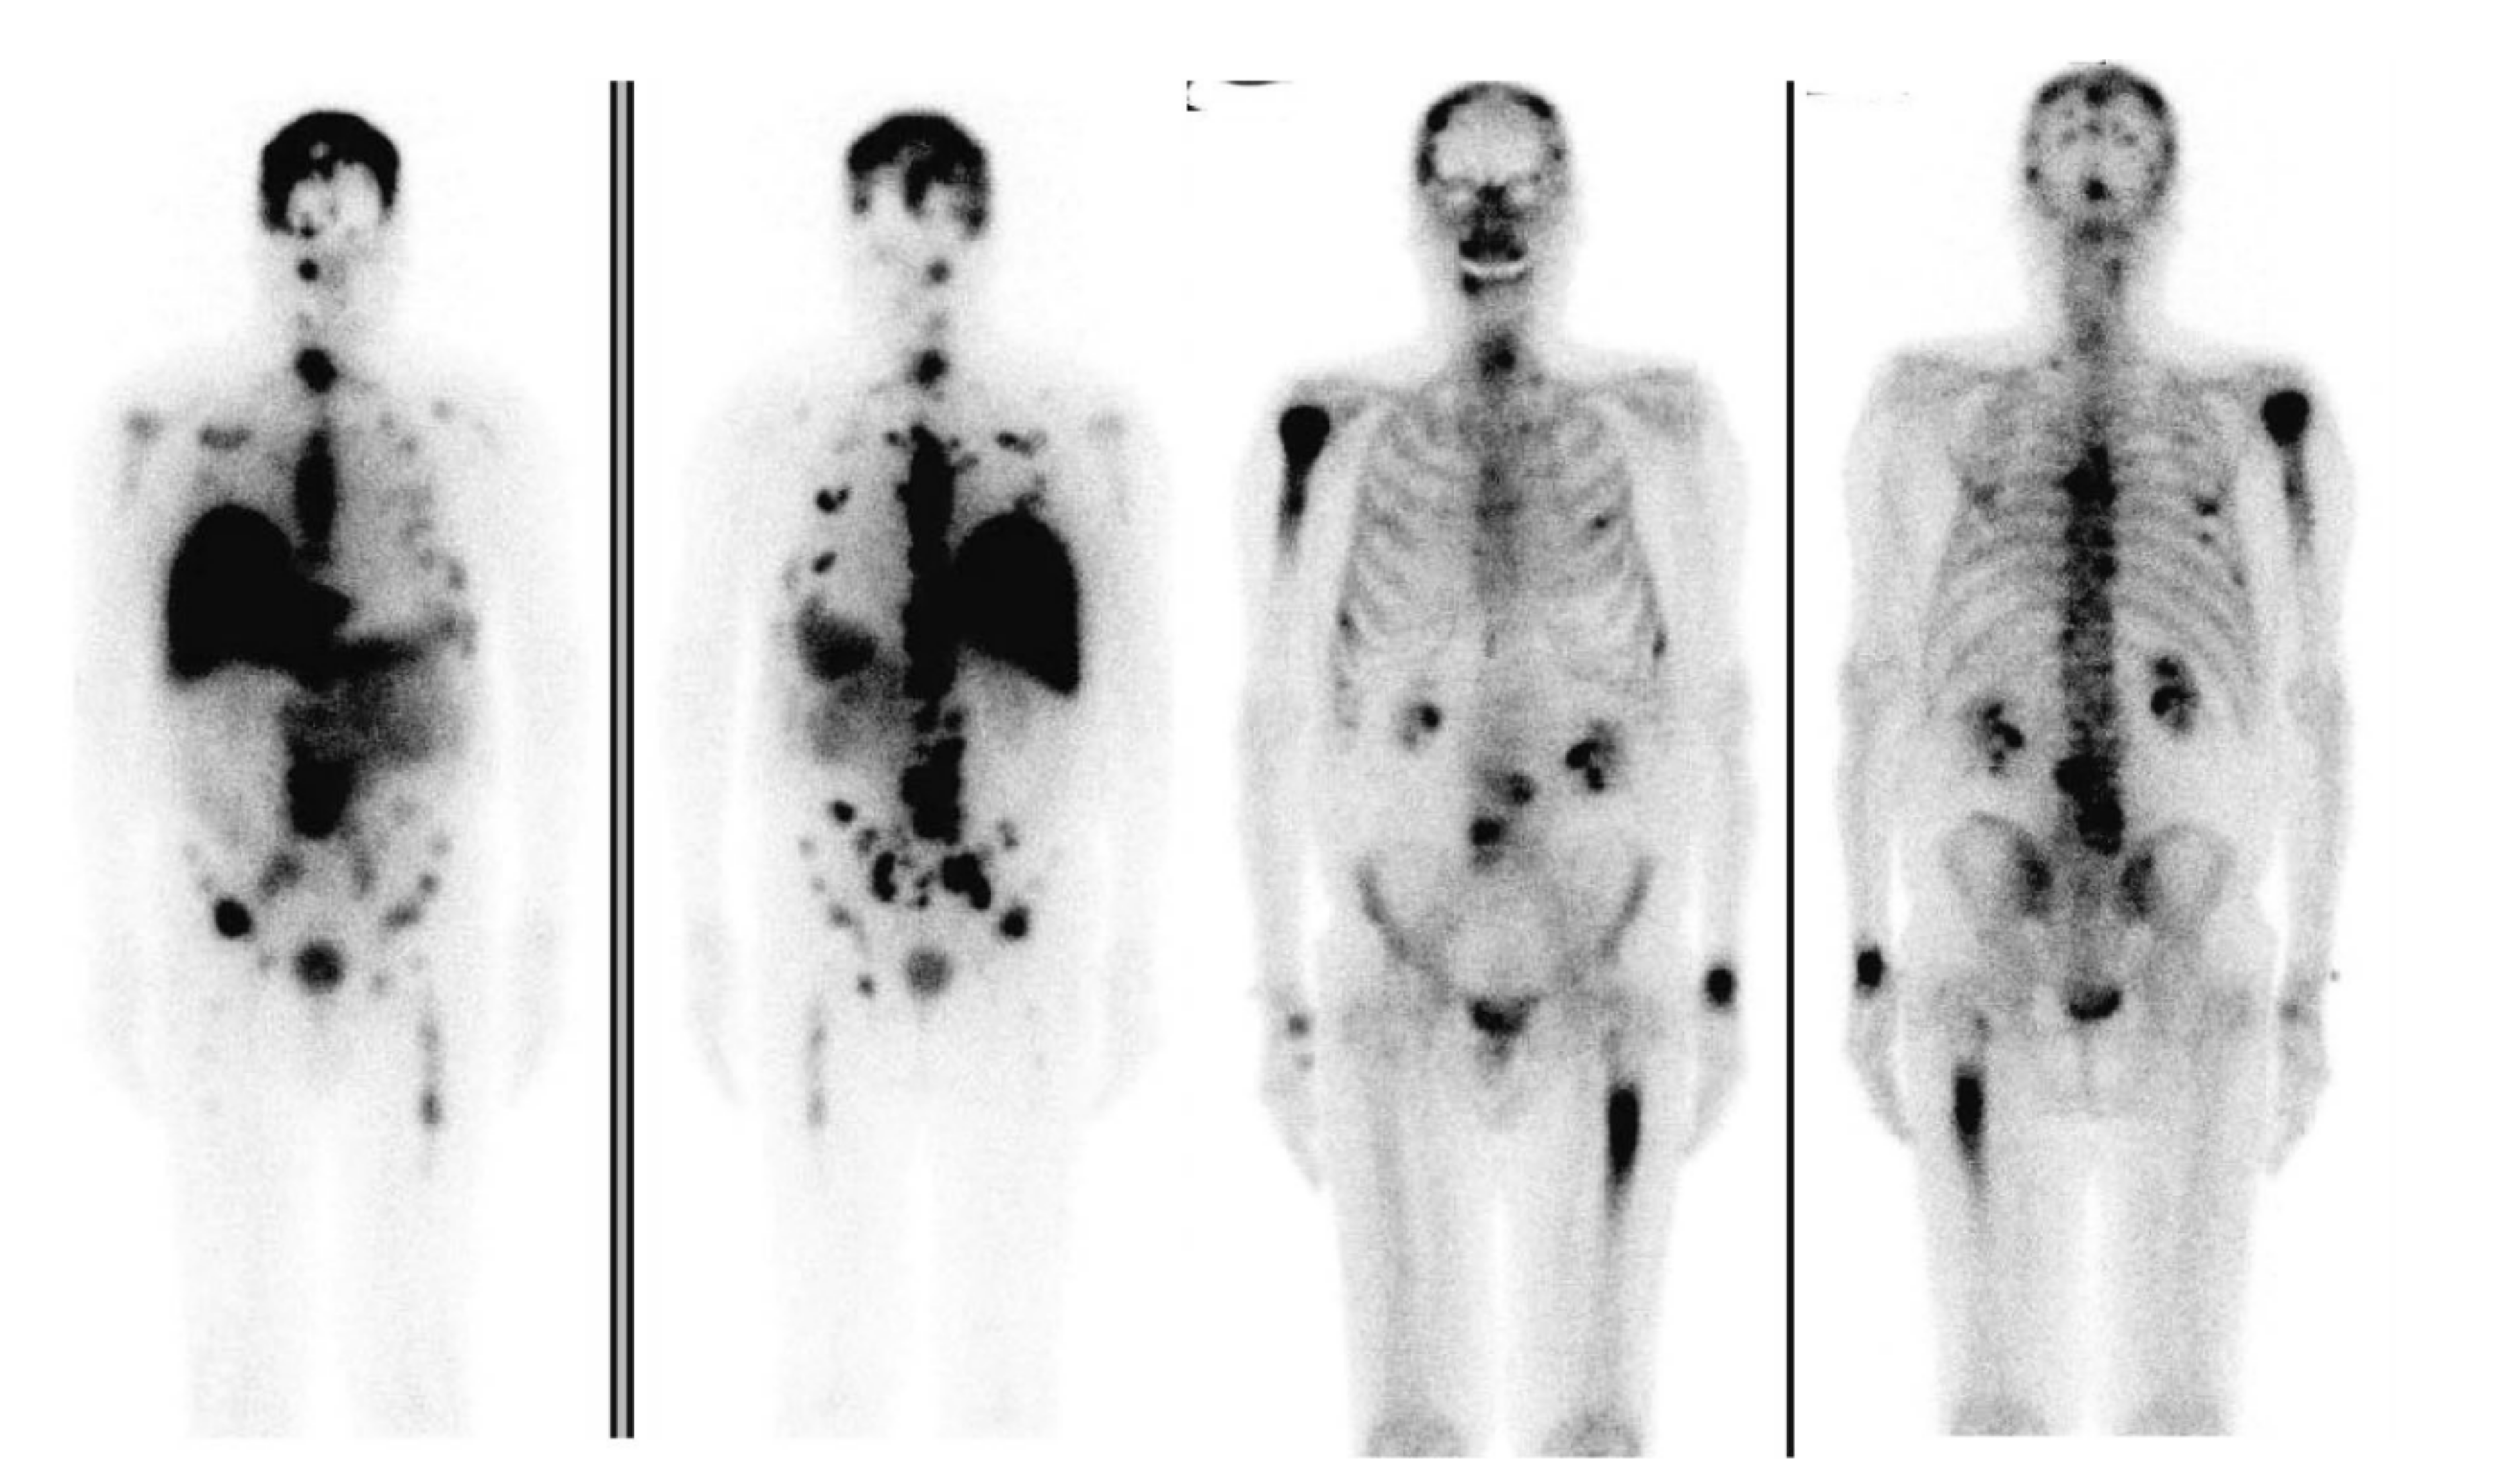

- Bensch, F.; Van der veen, E.L.; Lub-de Hooge, M.N.; Jorritsma-Smit, A.; Boellaard, R.; Kok, I.C.; Oosting, S.F.; Schröder, C.P.; Hiltermann, T.J.N.; Van Der Wekken, A.J.; et al. 89Zr-atezolizumab imaging as a non-invasive approach to assess clinical response to PD-L1 blockade in cancer. Nat. Med. 2018, 24, 1852–1858. [Google Scholar] [CrossRef]

- Niemeijer, A.N.; Leung, D.; Huisman, M.C.; Bahce, I.; Hoekstra, O.S.; van Dongen, G.A.M.S.; Boellaard, R.; Du, S.; Hayes, W.; Smith, R.; et al. Whole body PD-1 and PD-L1 positron emission tomography in patients with non-small-cell lung cancer. Nat. Commun. 2018, 9, 4664. [Google Scholar] [CrossRef]